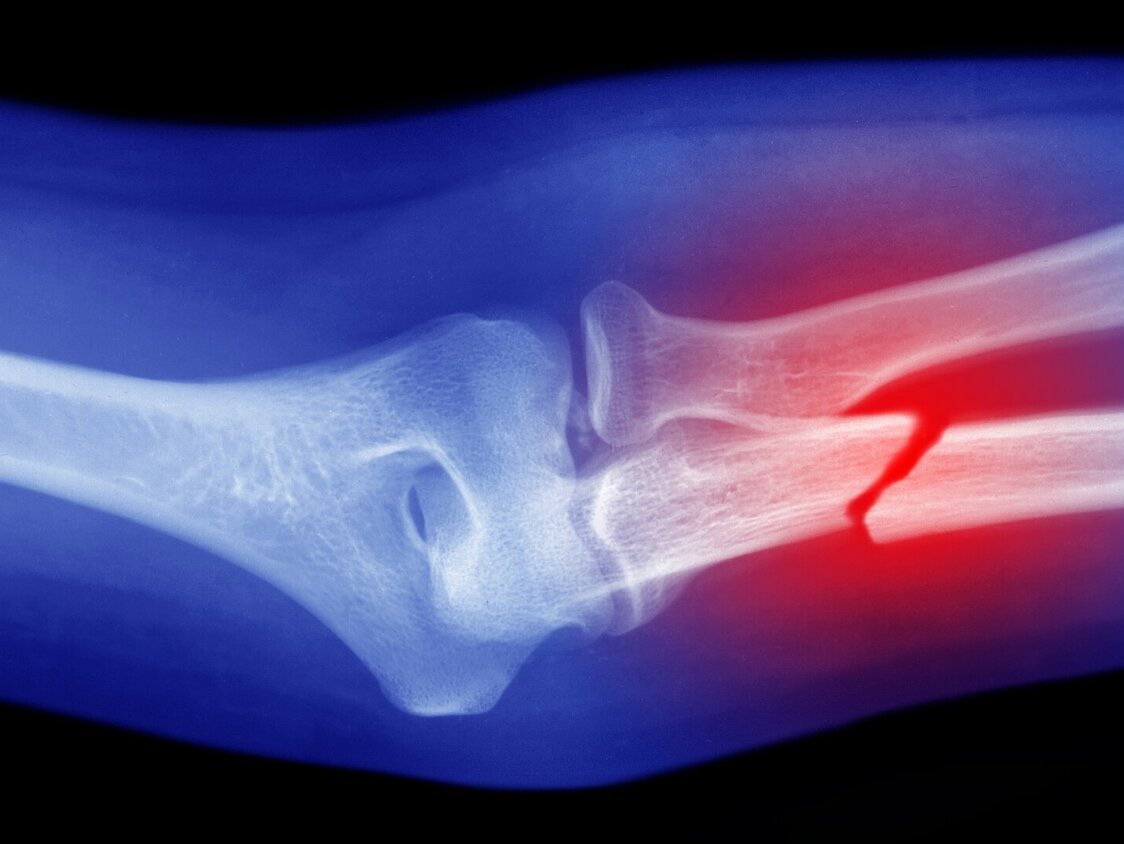

Durch zu starke Belastungen und externe Krafteinwirkungen können Knochenrisse, -Brüche oder -Zersplitterungen entstehen. Dabei werden drei gängige Arten von Knochenbrüchen unterschieden:

- Komplizierter, geschlossener Knochenbruch: In diesem Fall ist der Knochen nicht glatt durchgebrochen, sondern kann verschoben (disloziert) oder deformiert sein. Es besteht auch die Möglichkeit eines gesplitterten Knochens. In solchen Fällen kann es erforderlich sein, den Bruch in einer Operation zu richten.